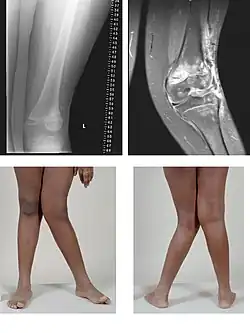

A very severe case of genu valgum of the left knee following bone cancer treatment

Genu valgum, commonly called "knock-knee", is a condition in which the knees angle in and touch each other when the legs are straightened.[1] Individuals with severe valgus deformities are typically unable to touch their feet together while simultaneously straightening the legs. The term originates from Latin genu 'knee' and valgus 'bent outwards', but is also used to describe the distal portion of the knee joint which bends outwards and thus the proximal portion seems to be bent inwards.

Mild genu valgum is diagnosed when a person standing upright with the feet touching also shows the knees touching. It can be seen in children from ages 2 to 5, and is often corrected naturally as children grow. The condition may continue or worsen with age, particularly when it is the result of a disease, such as rickets.[2] Idiopathic genu valgum is a form that is either congenital or has no known cause.